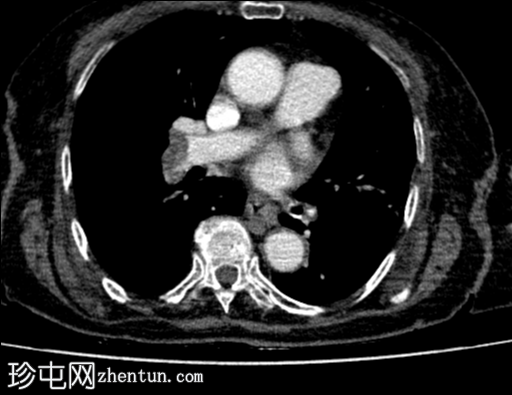

C+ CTPA

冠状位

CTPA显示:

双侧肺动脉主干均可见大片充盈缺损,右侧上、下主干及左侧下叶主干可见闭塞

双肺清晰,可见肺叶少血,左上肺可见局灶性胸膜下条索状萎陷

心脏增大

由于食管裂孔扩大,胃位于后纵隔,无胃扭转征象